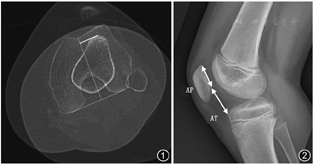

对于成功的MPFL重建手术,患者选择正确则是成功的起点。Sanchis-Alfonso[18]认为单纯行MPFL重建手术患者的纳入标准应为:(1)长期髌骨外侧不稳,至少两次髌骨外侧脱位史或麻醉状态下检查发现髌骨脱位;(2)胫骨结节股骨滑车沟距离(TTTG)(图1)超过20 mm;(3)膝关节屈曲30°时恐惧试验阳性;(4)髌骨Caton-Deschamps指数(图2)<1.2,A型滑车畸形。

为了保证在膝关节屈曲时髌骨良好的运动轨迹,正确的股骨止点则显得格外重要。尸体解剖研究显示,非解剖股骨止点重建会导致膝关节屈曲过程中髌股关节面接触力变大,相应的重建失败率则随之升高[19,20]。通过影像学方法或触摸解剖学结构可确定重建韧带股骨的止点。目前应用较多的是Stephen及Schöttle发明的影像学定位法。Stephen提出Stephen指数,将股骨内侧髁前后长度作为100%,那么解剖学止点则在距离前方60%处、距离后方40%处、距离远端50%处[10,21]。Schöttle等[22]所发明的定位点可根据膝关节侧位片确定,其位置定位于1个直径5 mm的圆环,圆心位于股骨后外侧皮质切线上1.3 mm,股骨后外侧皮质与外侧髁连线处做上述切线垂线下2.5 mm。但Sanchis-Alfonso等[23]及Ziegler等[24]提出,就算术中摄标准侧位片,也无法保证重建止点的准确性。因此Fujino等[25]提出使用术中延长切口来确定最佳的重建止点,所参考的解剖是大收肌肌腱。术中很容易定位大收肌肌腱,其起点位于MPFL的外侧,位于收肌结节顶点远端(10.6±2.5)mm,同时与股骨轴线平行。在收肌结节止点和内侧髁间明显的凹点则是MPFL股骨止点的位置,当然最终钻孔置入导针仍需影像学协助,术中透视摄片可防止导针穿破后方皮质。